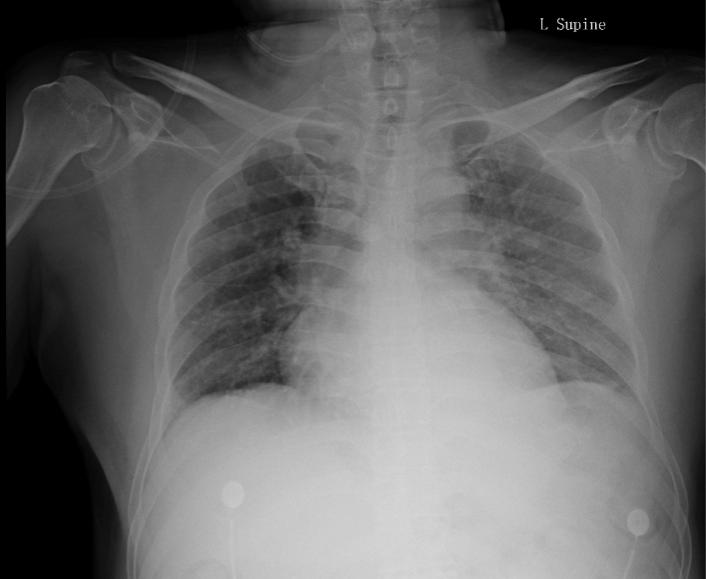

患者是在下午3点左右完成的手术,手术当天夜里10点出现了胸痛的症状,胸痛表现为与呼吸相关的刺痛。为患者完善了胸片,未见气胸,未见心包积液征象(图1)。这是典型的房颤患者围术期管理,因为进行了锁骨下静脉穿刺,因而需考虑到穿刺相关并发症的可能如气胸,但胸片无阳性发现,基本可除外。另外需要考虑到的致命并发症就是心包填塞,患者无心率快、血压低等典型表现,胸片未见心影增大,也不支持。

图1:患者开始出现胸痛,完善的胸片,未见气胸和心包积液表现,但回顾来看,左侧胸腔看似密度增高